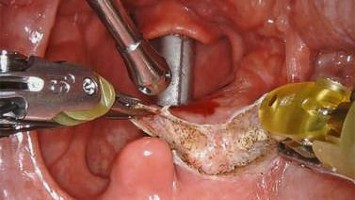

Flächendeckende Innovation

Vor wenigen Jahren in Österreich noch eine exotische Operationsmethode – heute annähernd flächendeckend im Einsatz: Roboterchirurgie ist aus der urologischen Therapielandschaft nicht mehr wegzudenken.

Minimalinvasive Operation first

Die transorale Roboterchirurgie (TransOral Robotic Surgery, TORS) bietet bei ausgesuchten Tumoren des oberen Respirationstrakts die Möglichkeit einer minimalinvasiven Chirurgie. Die Vor- und Nachteile dieser Operationsmethode sollen hier kurz erläutert werden.